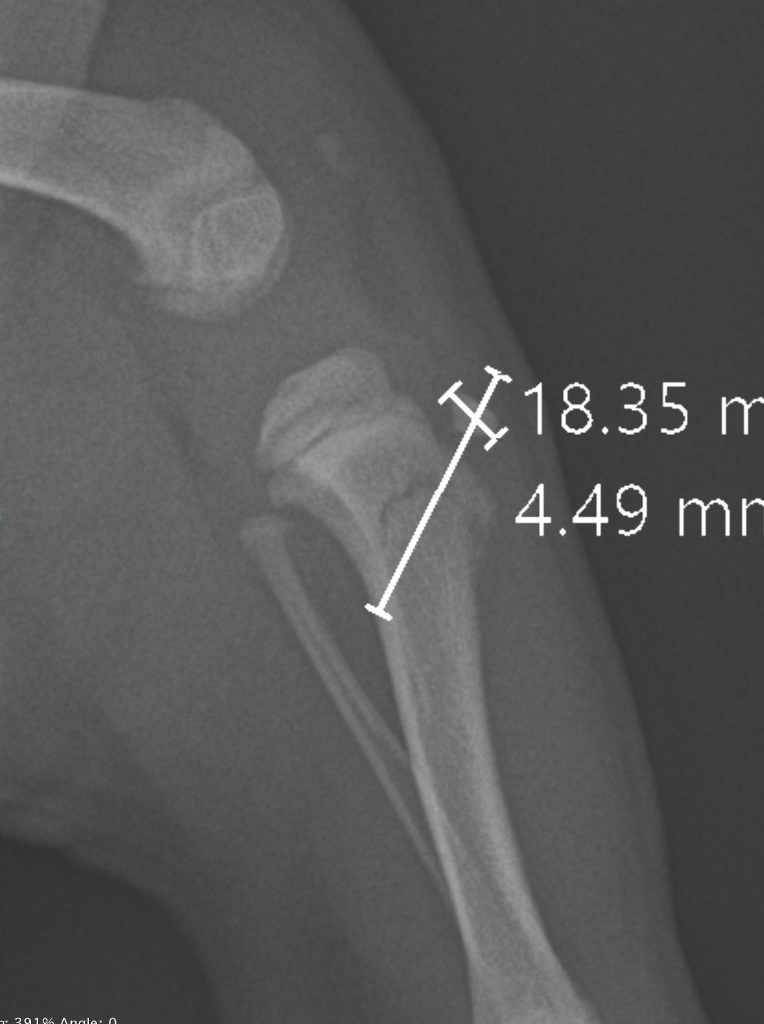

↑脛骨の側面像:脛骨近位部が若木骨折していました

↑手術前に骨折の整復計画を立てます